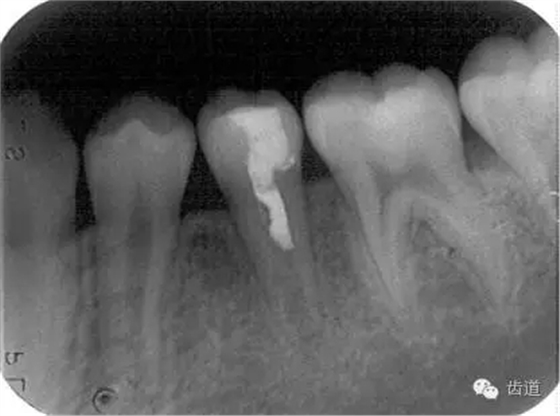

術(shù)后

術(shù)前

術(shù)后199日

術(shù)后1084日